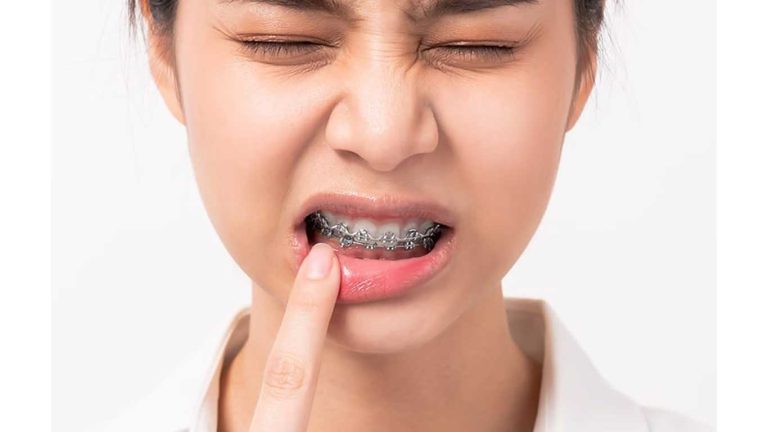

صاف کردن دندان کج یکی از اصلی ترین اهداف در دندانپزشکی زیبایی و ارتودنسی است که می تواند تاثیر شگرفی بر زیبایی لبخند و اعتماد به نفس افراد داشته باشد. دندان های نامرتب، چه به صورت یک دندان کج و چه به صورت شلوغی گسترده، نه تنها از نظر ظاهری ناخوشایند هستند، بلکه می توانند سلامت دهان و دندان را نیز به خطر بیندازند. خوشبختانه، با پیشرفت های چشمگیر در علم دندانپزشکی، امروزه روش های متنوع، کارآمد و گاهی سریعی برای اصلاح این مشکل وجود دارد. این مقاله به صورت جامع به بررسی دلایل، عوارض و انواع روش های درمانی برای این عارضه می پردازد. با راهنمایی های دکتر کاظم دالایی متخصص ارتودنسی در شریعتی تهران، می توانید با آگاهی کامل، بهترین مسیر را برای دستیابی به لبخندی بی نقص و مرتب انتخاب کنید.

هدف نهایی از صاف کردن دندان کج، تنها ایجاد یک لبخند زیبا نیست، بلکه دستیابی به یک بایت صحیح و عملکردی، تسهیل بهداشت دهان و دندان و در نهایت، ارتقای سلامت کلی سیستم جونده است. این درمان به بهبود شکل صحیح قرار گرفتن دندانها روی هم کمک شایانی می کند.

عوارض نادیده گرفتن دندان های کج

- افزایش ریسک پوسیدگی و بیماری لثه: تمیز کردن دندان های کج و روی هم رفته بسیار دشوار است. این امر باعث تجمع پلاک ارتودنسی یا پلاک دندانی و افزایش خطر پوسیدگی و التهاب لثه در ارتودنسی و بدون آن می شود.

- مشکلات مربوط به بایت و جویدن: دندان های کج می توانند باعث ایجاد تماس های نامناسب و اختلال در عملکرد جویدن شوند.

- سایش غیر طبیعی دندان ها: نیروهای نامتعادل جویدن می تواند منجر به ساییدگی زودرس مینای دندان ها گردد.

- مشکلات مفصل فک (TMJ): یک بایت نامناسب می تواند در بلند مدت به مفصل گیجگاهی فکی فشار آورده و باعث بروز درد و ناراحتی شود.

- کاهش اعتماد به نفس: تاثیر روانی داشتن دندان های نامرتب و عدم رضایت از ظاهر لبخند را نباید نادیده گرفت.

آیا صاف کردن دندان کج درد دارد؟

درد ارتودنسی معمولا به صورت یک فشار یا ناراحتی خفیف در چند روز اول پس از قرار دادن یا تنظیم دستگاه احساس می شود. این درد کاملا طبیعی و موقتی است و نشانه حرکت دندان ها است. این حس با مسکن های معمولی به راحتی کنترل می شود.